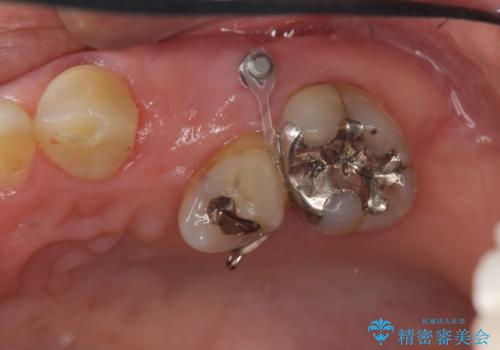

- 左上の歯の喪失し噛みにくいことの改善、歯を入れたいと希望され来院されました。

インプラント治療を行うには隙間が狭すぎるためブリッジか入れ歯をご提案したところ、取り外しの必要な入れ歯は希望されずブリッジを用いて機能・審美性の改善を行っていくこととなりました。

ブリッジの長期的な予後のためには支台となる歯の位置・清掃性が重要となりますが、今回ブリッジを製作するにあたり位置の悪い左上小臼歯を補綴前小矯正を行い位置を改善します。